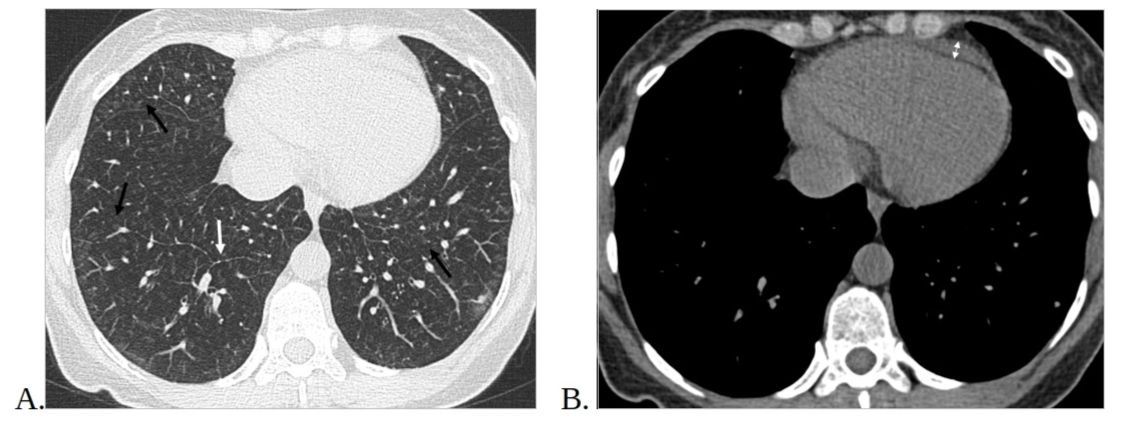

4. Рис.4. МСКТ органов грудной клетки, аксиальные срезы. | |

6. Рис.6 МСКТ органов грудной клетки, аксиальные срезы. | |